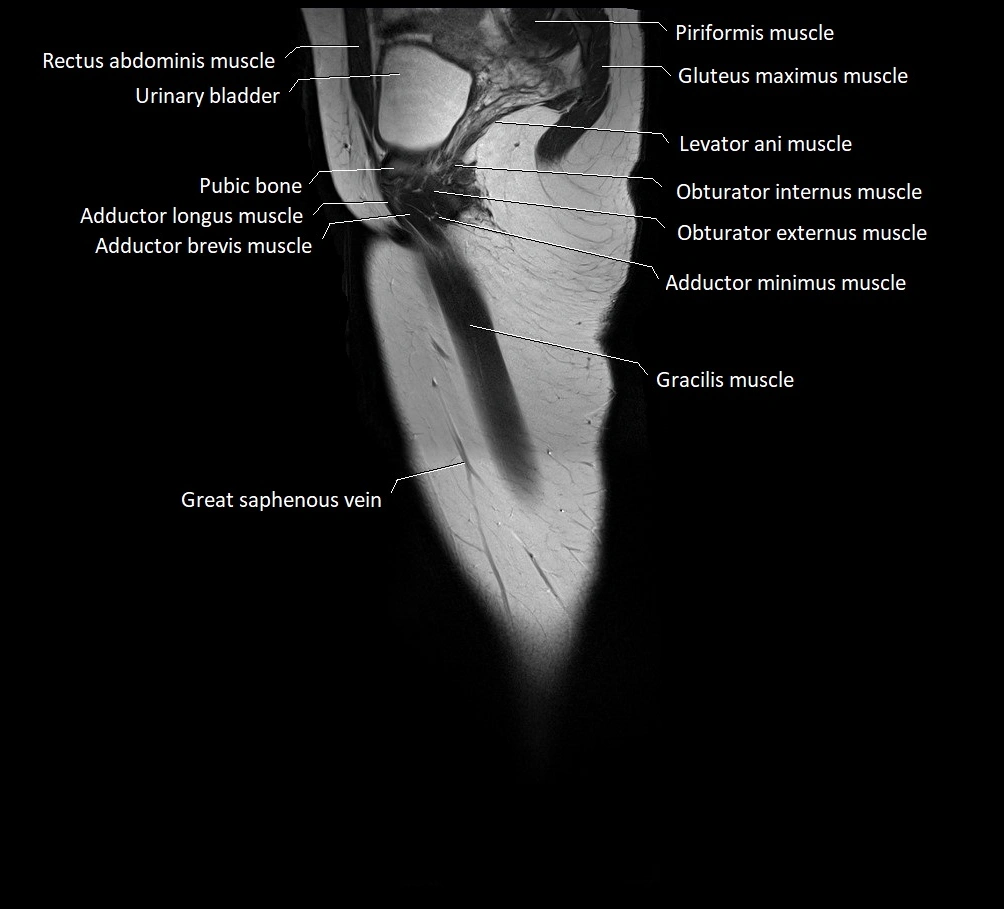

- Adductor brevis muscle

- Adductor longus muscle

- Adductor minimus muscle

- Gracilis muscle

- Levator ani muscle

- Obturator externus muscle

- Obturator internus muscle

- Pubic bone

- Pyramidal muscle (pyramidalis muscle)

- Quadratus femoris muscle

- Urinary bladder